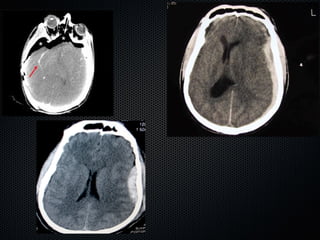

Alteração profunda da consciência

“Toilet” traqueobrônquico

Disfunção pulmonar ou multi-orgânica

associada com insuficiência respiratória

(Sepse grave/Choque séptico, lesão

anatômica do pulmão, alterações de gases

sangüíneos, etc...)